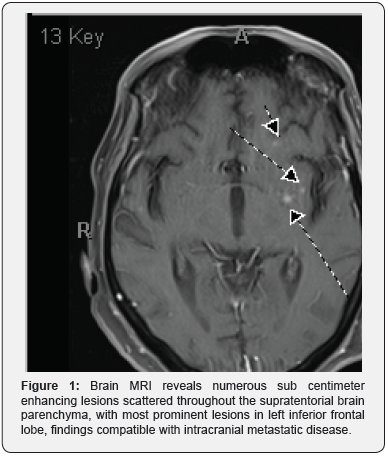

A 62-year-old Caucasian man with history of coronary artery disease and bypass graft presented with progressive fatigue, anorexia, and a 75-lb weight loss over a 3-month period. Diagnostic workup by his primary care physician had included CT scans of chest and abdomen/pelvis with contrast that showed bilateral granular ground-glass opacities in lungs as well bilateral adrenal masses and hepatosplenomegaly. Subsequent brain MRI then revealed multiple enhancing lesions, which were concerning for metastasis (Figure 1). Abdominal MRI also revealed a 39.6mm x 33mm left adrenal mass that was concerning for metastasis given the patient’s associated complaints of splenomegaly and pancytopenia (Figure 2). He was then referred to an oncologist, who proceeded with outpatient workup for presumed malignancy, but because of progressive fatigue, hypotension and hypoglycemia, he was admitted to an outside hospital. Later, he was transferred to our institution for further management. On admission, he was noted have pancytopenia and hypercalcemia (Ca=11.7).

The diagnosis of CNS histoplasmosis can be challenging. Multiple tests for diagnosis of H. capsulatum in the CNS are necessary due to the variability in symptoms and the number of false-negative tests. Culturing of the CSF or CNS parenchymal tissue is the gold standard for diagnosis of CNS histoplasmosis. Antigen detection in CSF culture has a sensitivity of 38% and a specificity of 98%. Additional tests for H. capsulatum polysaccharide antigen (HPA) in CSF, urine, or serum can be performed to aid in the diagnosis and monitor response to therapy. The sensitivity of HPA in the CSF is 38% in all patients and 67% in patients with AIDS. However, the sensitivity of Histoplasma antigen in Urine and Serum is 71%, and 38% respectively [6,8]. Antibody testing in CSF and serum has 80 to 89% and 92% sensitivity, respectively, although these tests are susceptible to cross-reactivity leading to false positives. Serologic testing is especially difficult with AIDS patients and often provides false negatives even with an active infection. In addition, positive CSF culture results are similar to results seen in other fungal and tuberculous meningitis. Therefore, other tests must be performed. MRI often shows single or multiple ring-enhancing lesions in CNS histoplasmosis. However, ringenhancing lesions can also be indicative of an abscess, a necrotic tumor, subdural and epidural empyema or toxoplasmosis. Histoplasmosis should be considered if symptoms correlate to that of the infection or if the patient has had exposure to an endemic area [6].

In conclusion, clinicians should have a low threshold for considering CNS histoplasmosis as a cause for brain lesions. CNS histoplasmosis is a rare condition but requires prompt diagnosis in order to initiate appropriate treatment regimen. Our case depicts a patient who initially presented with concerns for metastatic disease in setting of hypercalcemia, pancytopenia, significant weight loss and generalized weakness. Diagnostic testing further revealed multiple enhancing lesions in brain and bilateral adrenal masses, which was strongly suspicious of malignancy. A subsequent adrenal gland biopsy was crucial in demonstrating multiple yeasts and thus, aiding in diagnosis. In the context of the aforementioned biopsy results and the typical findings of granulomatous involvement of histoplasmosis presenting with hypercalcemia, there was strong evidence to support a diagnosis of disseminated histoplasmosis. Our patient did not have any significant risk factors, he was a normal host with no underlying immunodeficiency disorder, and he did not have significant exposure history like spelunking or exposure to bats or bird droppings. Overall, we present a case of disseminated histoplasmosis with CNS and adrenal involvement in an immunocompetent host with a unique presentation as disseminated histoplasmosis with enhancing CNS lesions.